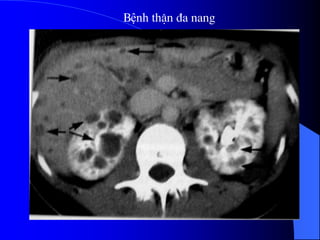

3.5. Tháûn âa nang

Tháûn âa nang laì bãûnh di truyãön.

Nang coï nguäön gäúc tæì nephron. Thæåìng

xaøy ra åí hai tháûn, nãúu tháúy tháûn âa nang mäüt

bãn thç bãn kia coï báút thæåìng kên âaïo hån,

nhæîng nang nhoí hån.

Khoaíng 50% træåìng håüp kãút håüp våïi

nhæîng báút thæåìng khaïc nhæ nang gan, nang

tuûy, nang laïch, tuïi phçnh âäüng maûch naîo.

- Trãn phim buûng coï thãø tháúy boïng tháûn

låïn gáy dáúu hiãûu âáøy håi trong ruäüt (häüi

chæïng khäúi), xoïa båì cå thàõt læng cháûu.

- Trãn NÂTM mä tháûn caín quang khäng âäöng

nháút. Khi ÂBT nhuäüm âáöìy TCQ tháúy bãø

tháûn heûp theo chiãöu ngang, tàng theo chiãöu

doüc. Caïc âaìi tháûn bë keïo daìi, maính deí, lãûch

hæåïng do nhiãöu nang âeì vaìo.

- Trãn siãu ám phaït hiãûn tháûn âa nang, ngay

caí åí giai âoaûn såïm, tháûn låïn våïi ráút nhiãöu

nang nhoí. Khi nang bë nhiãùm khuáøn hay

xuáút huyãút seî tháúy cáúu truïc ám cuía caïc nang

khäng âäöng nháút, thaình nang daìy, väi hoïa.

Siãu ám âäöng thåìi coï thãø tháúy nang åí gan

hoàûc tuûy, laïch trong häüi chæïng Von Hippel -

Lindau.